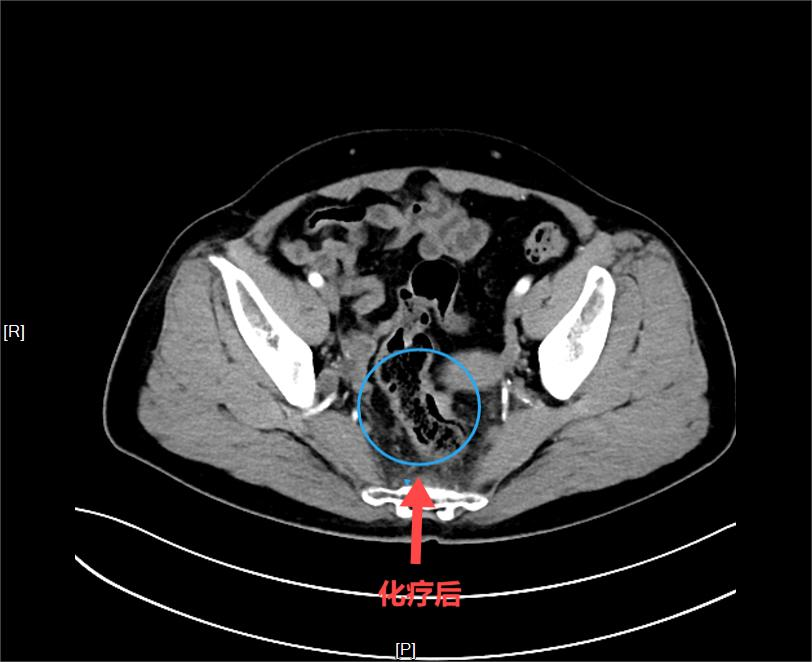

令人欣慰的是,经过四次两疗程的转化治疗后,刘阿姨明显感觉下腹部好像少了一样东西,身体轻松了好多。经过再次的增强CT评估,发现直肠肿瘤瘤体明显缩小,CT上几乎不可见,转移的淋巴结也明显缩小,显示出理想的治疗效果。

图片

▲化疗后